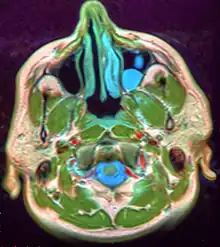

.JPG.webp)

Microscopically, mucoceles appears as granulation tissue surrounding mucin. Since inflammation occurs concurrently, neutrophils and foamy histiocytes usually are present. On a CT scan, a mucocele is fairly homogenous, with an attenuation of about 10-18 Hounsfield units.[5]